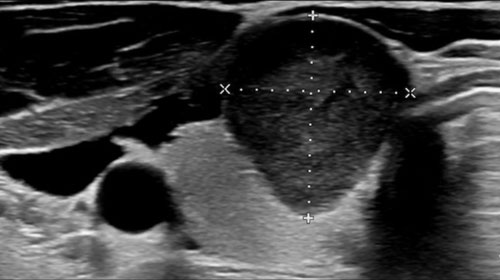

TI-RADS - Thyroid Imaging Reporting and Data System

TI-RADS